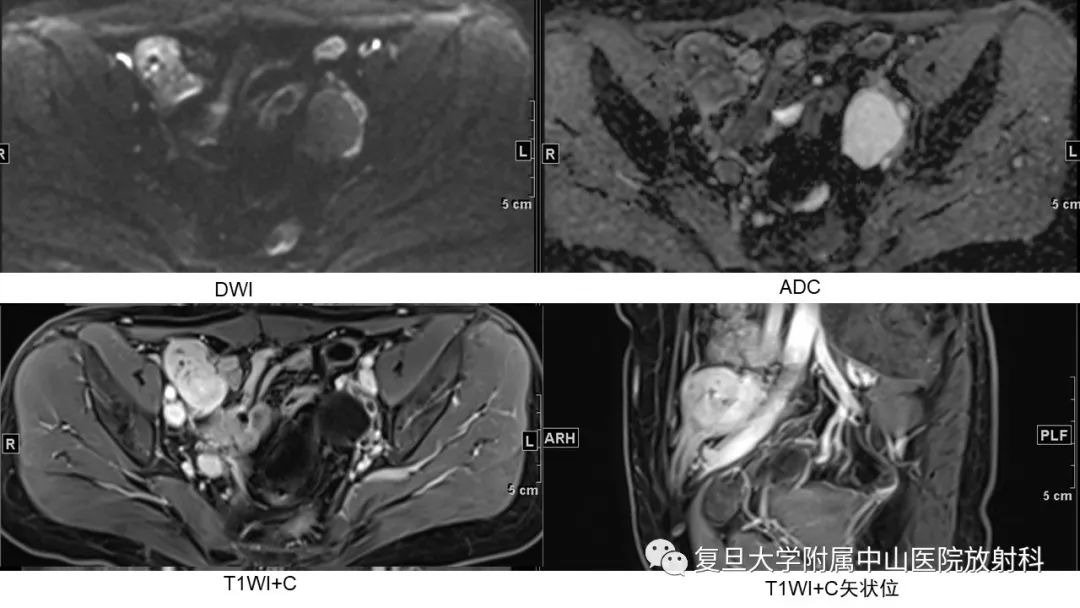

【病例】子宫腺肌瘤1例MR影像

【病例】子宫腺肌瘤1例MR影像-2